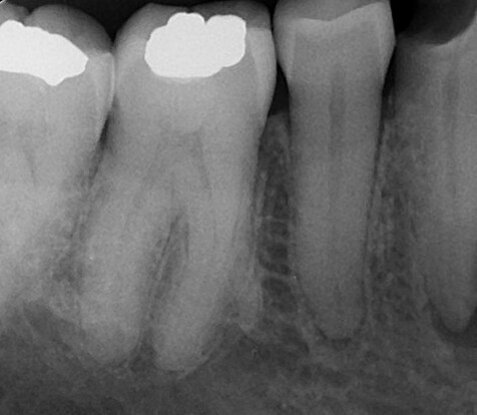

Fig. 9: Post-op radiograph.

A radiograph to confirm the final working lengths was carried out with an endodontic ring holder and the VDW. ROTATE 15.04 and 20.05 files (Figs. 5 & 6). The last instrument at the apex was the 25.04 file owing to its flexibility and reduced core (compared with the 25.06 file) using the same strategies as in the previous steps. Final rinses with EDTA solution and sodium hypochlorite were followed by activation of the solution with a pre-bent EDDY tip (VDW, Fig. 7) for 20 seconds. The canals were then dried and filled with AH Plus (Dentsply Sirona) and two gutta-percha cones matching the VDW.ROTATE instruments (VDW) and made of a more heat-conductive gutta-percha with a lower melting temperature using the continuous wave technique up to the bifurcation. A radiograph was taken (Fig. 8) to check the root canal fillings and then a fibre post and core build-up were carried out. The final radiograph showed good filling of the root canals with small extrusions of the sealer through the buccal foramen and a lateral canal (Fig. 9). The patient was referred to her dentist for permanent restoration of the tooth. Six months of follow-up was planned in order to control the outcome of the treatment.